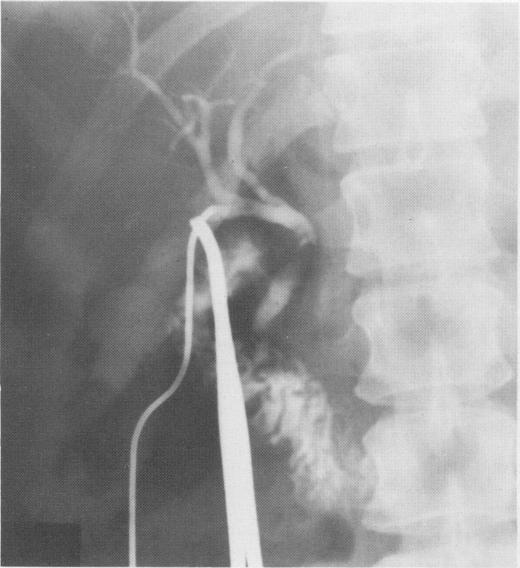

Per-operative cholangiography and post-cholecystectomy biliary strictures.

A series of 78 patients with post-cholecystectomy biliary strictures have been examined. The majority (71%) did not have per-operative cholangiography at the time of initial cholecystectomy. Of the remainder, inadequate views were obtained in two patients and incomplete information was associated with subsequent common bile duct damage. In addition the study was performed after the common bile duct had been transected in a further two cases. The use of per-operative cholangiography in patients undergoing cholecystectomy is advocated, and the advantages and disadvantages of such an approach examined.